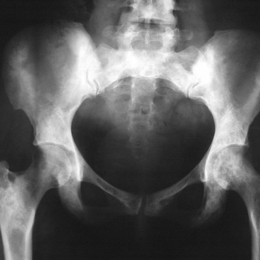

Radiographic imaging is used to help form a diagnosis. These include X-Ray, MRI, CT and Bone Scans.

An example of a X-Ray is shown.